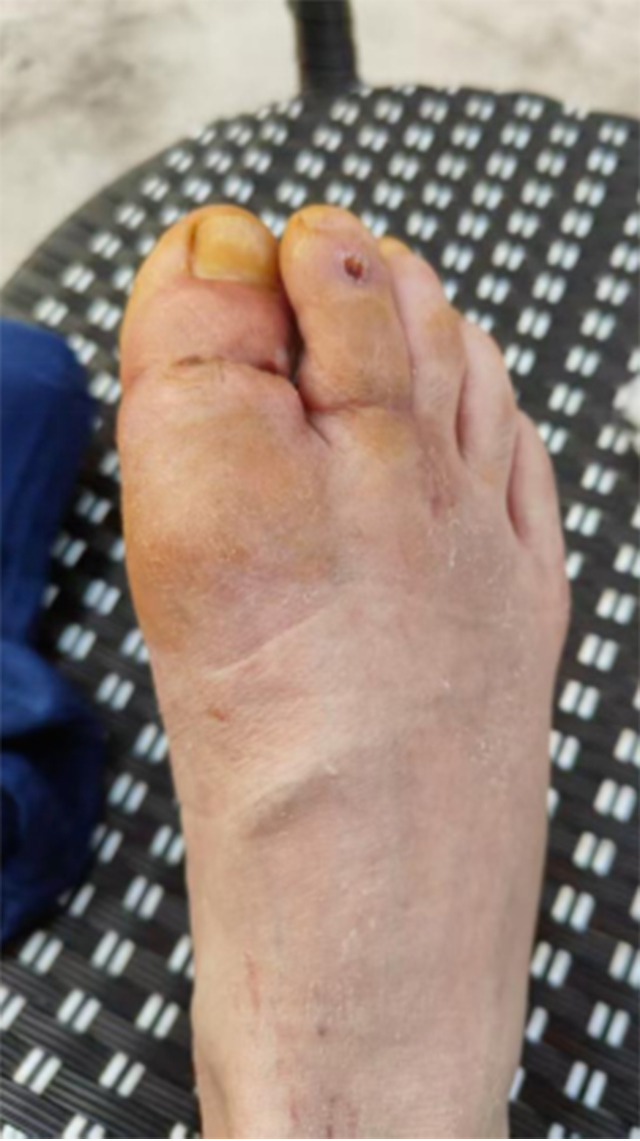

手术历时7个多小时,直到半夜12点才结束。术后予以抗感染、抗血管痉挛、补液扩容等治疗。最终保住了小李右足的两根脚趾。